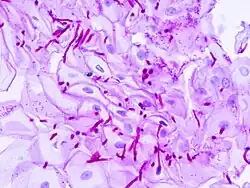

In most cases, the diagnosis is established based on response to therapy. Patients in whom esophageal candidiasis is suspected should receive a brief course of antifungal therapy with fluconazole. If the infection resolves after treatment with fluconazole, then the diagnosis of esophageal candidiasis is made and no further investigation is needed. However, if the infection persists or if there are other factors involved which may warrant further investigation, then patient will undergo an esophagogastroduodenoscopy if it is safe to do so. Endoscopy often reveals classic diffuse raised plaques that characteristically can be removed from the mucosa by the endoscope. Brushing or biopsy of the plaques shows yeast and pseudohyphae by histology that are characteristic of Candida species.

Esophageal candidiasis stained by periodic acid-Schiff procedure -

Esophageal candidiasis stained by periodic acid-Schiff procedure